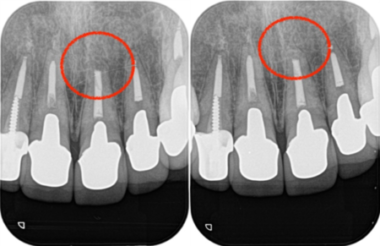

当院にて詳しく診査を行ったところ、左上1番の歯に根尖性歯周炎(虫歯や歯髄炎が進行し、歯の根の先周辺の歯周組織に炎症が生じた状態)が確認されました。

この炎症が、患者様が感じていた違和感の主な原因であると診断しました。

レントゲン画像がこちらになります。